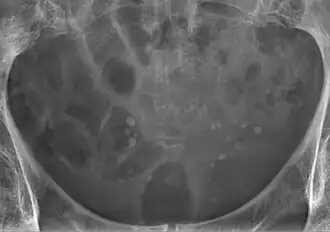

Een fleboliet, ook wel adersteen genoemd, is een kleine lokale, meestal ronde, calcificatie in een ader. Ze komen veelal voor in de aders van het onderste deel van het bekken en geven over het algemeen geen klachten. Op röntgenfotos zijn ze soms moeilijk te onderscheiden van nierstenen in de urineleiders.[1]

Flebolieten in het bekken komen voor bij ongeveer 44,2% van de mensen en meer bij vrouwen (50,1) dan mannen (37,3%). De hoeveelheid flebolieten neemt toe bij het ouder worden en ze komen verder vaker links voor dan rechts.[2] Flebolieten buiten het bekken komen voor bij ongeveer 2% van de mensen.[3]